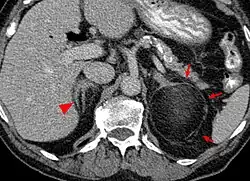

| An adrenal myelolipoma | |

Myelolipomas can present in the adrenal gland,[2] or outside of the gland.[3]

Most myelolipomas are unexpected findings on CT scans and MRI scans of the abdomen. They may sometimes be seen on a plain X-ray films.[4]